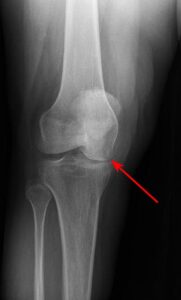

In children and adolescents, ankle fractures typically affect the tibia or fibula, often involving the growth plates—specialized areas of cartilage near the ends of long bones. Growth plates play a critical role in bone development, gradually hardening into solid bone as the child matures. However, because these growth plates are the last parts of the bones to solidify, they are particularly prone to injury and fractures. As adolescents approach the end of their growth phase, growth plates begin to close and harden, making them susceptible to transitional fractures during this maturing stage. Two common types of transitional ankle fractures are triplane fractures and Tillaux fractures, which require specific treatment approaches depending on their severity and location (refer to the Treatment section for more details)